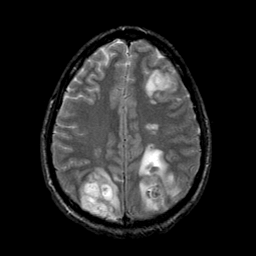

Sarcoma, MR Study #1 mr-t2 -- Slice #17